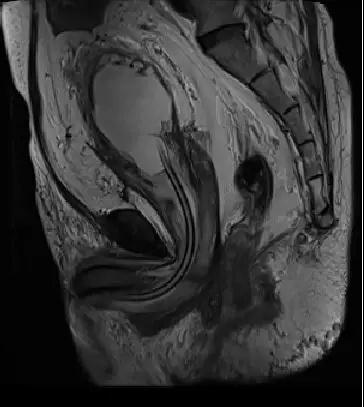

原以为是前列腺增生导致的上尿路积水,肾功能损害但细心的医生给病人查体发现,患者下腹部膨隆肛门指检未触及前列腺,这跟普通的前列腺增生症的病人并不相符

进一步完善泌尿系CT发现患者除了双肾重度积水,输尿管扩张之外盆腔有大量脂肪堆积

盆腔脂肪明显增多,前列腺抬高,膀胱挤压变形

盆腔脂肪增多症是一种原因不明的良性罕见病,是由于大量脂肪堆积于盆腔,包绕压迫膀胱下段、膀胱颈、直肠,使之变形、狭窄,并出现移位,造成膀胱颈部、输尿管下段、乙状结肠、直肠等梗阻改变